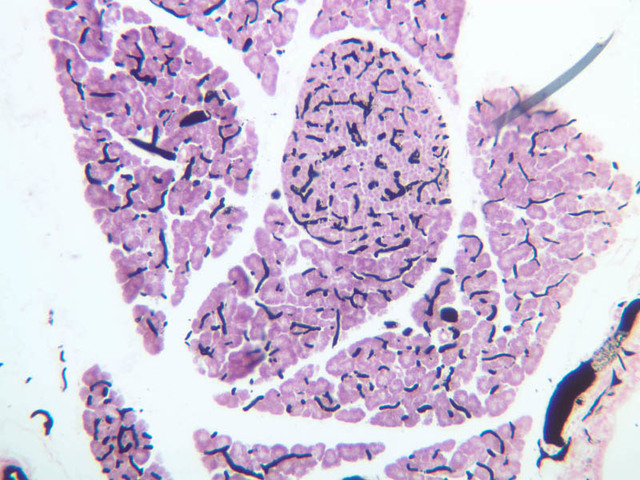

On the silver stained section of stillborn liver (Slide B-32 [10x, 20x, 40x]), examine the meshwork of reticular fibers that form a scaffolding for the hepatocytes and anchoring sites for the basement membrane of the sinusoidal lining.